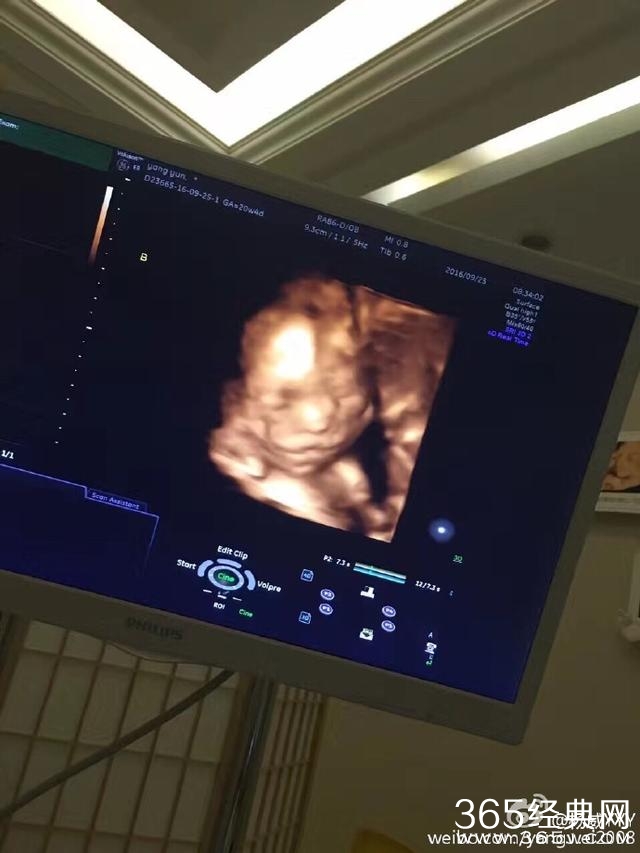

今晚杨威在微博晒出杨云所怀双胞胎的B超照片,并称:“一个像自己,一个像杨云。”暗示怀的是龙凤胎,这幸福秀的简直不要太甜蜜!!看来可爱杨阳洋很快就要有两个可爱的弟弟妹妹了。

可以从照片看出杨云腹中胎儿与杨威五官很像,怀了是龙凤胎,那可就真的满足了杨威的女儿梦啊,要知道女儿控的他之前非常希望能有一个小公主。观众为黄渤贡献了70亿票房,却只投6票给他,输给冯绍峰,心疼